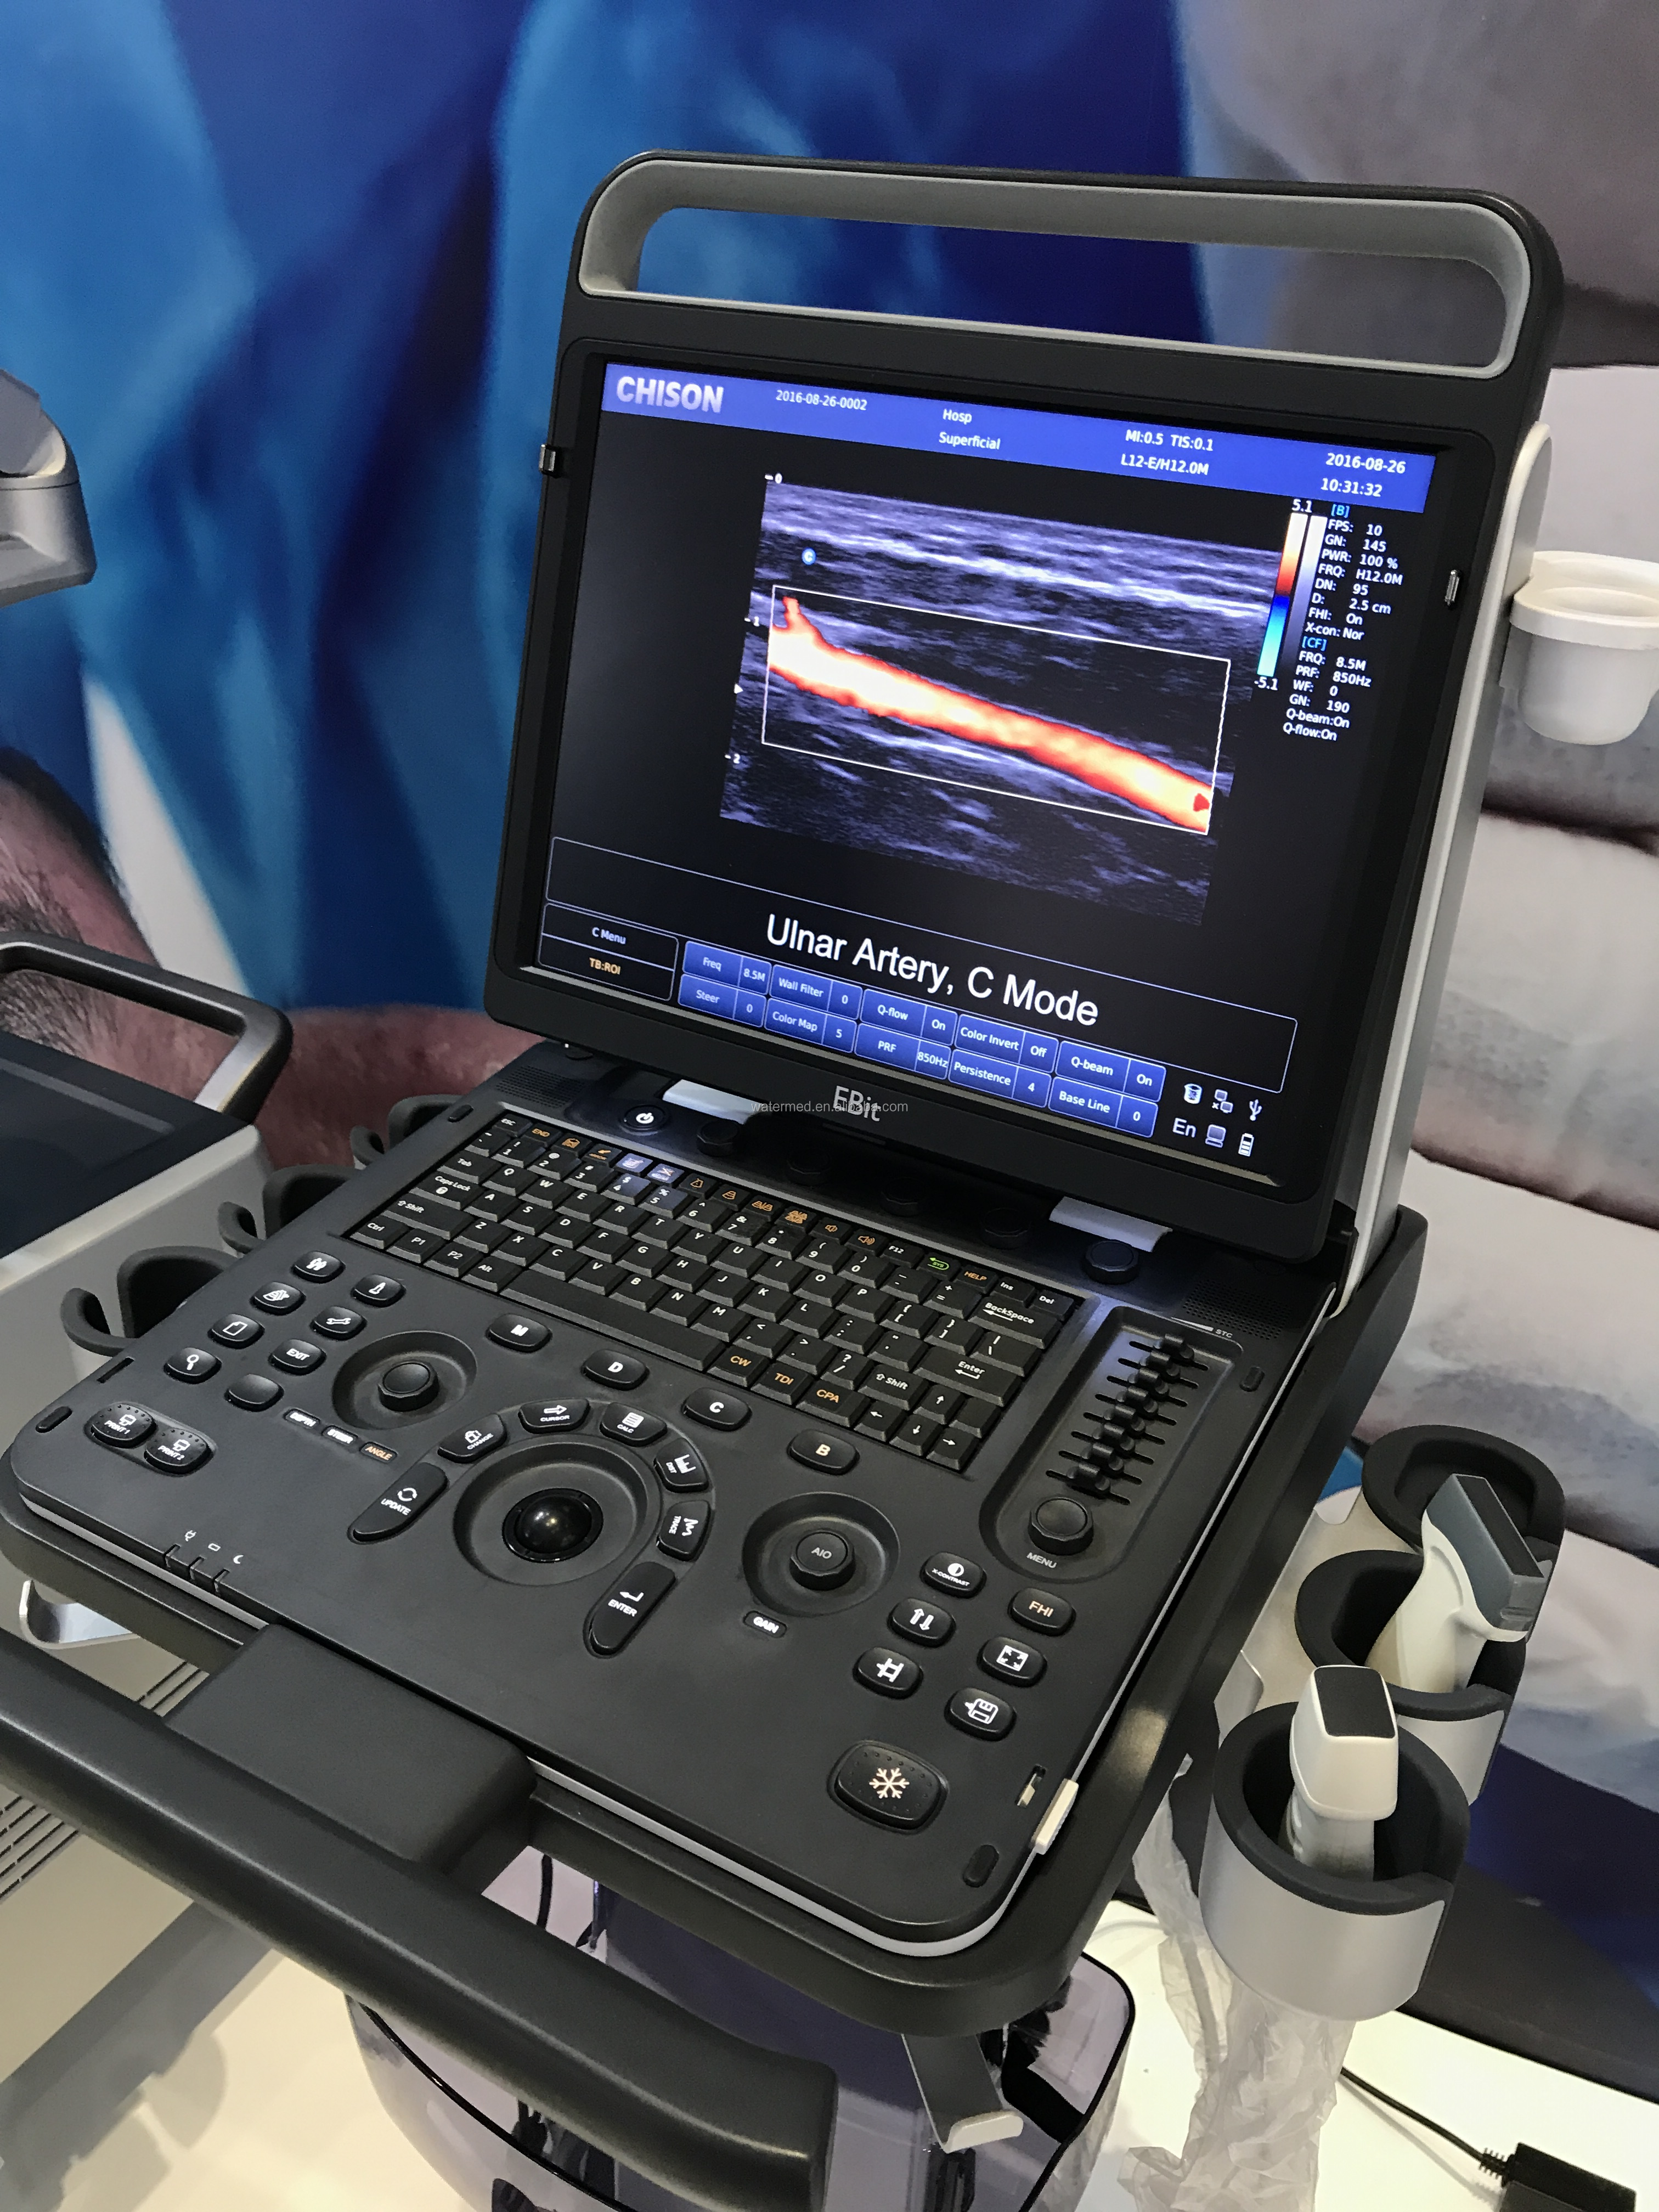

pulse inversion harmonic imaging

Harmonic signals are adequately preserved without degrading acoustic information, which allows the S9 to image high-level details and improve contrast resolution by reducing noise and clutter in the visualization of subtle lesions, small sites, blood vessels, etc.

Harmonic signals are adequately preserved without degrading acoustic information, which allows the S9 to image high-level details and improve contrast resolution by reducing noise and clutter in the visualization of subtle lesions, small sites, blood vessels, etc.